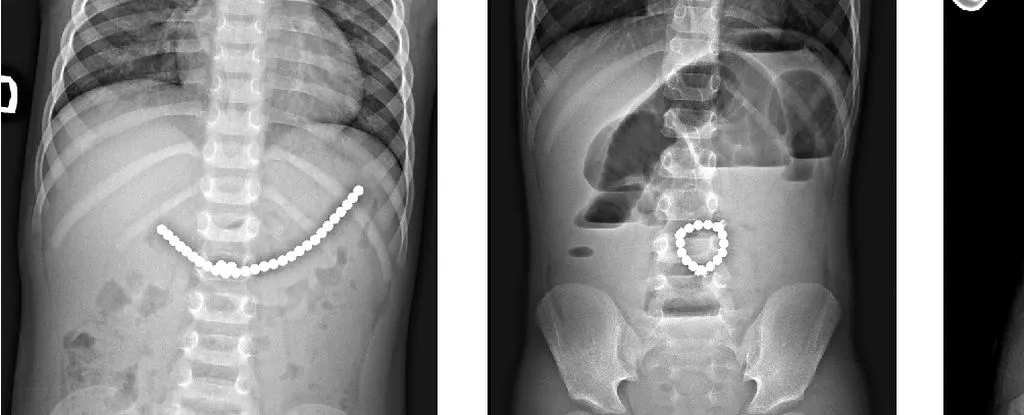

200 颗磁铁在患儿腹中形成了磁铁链。来源:Lekamalage et al., NZMJ, 2025

儿童吞食小型磁珠后的 X 光片。来源:Daškevičiūtė et al.,2017